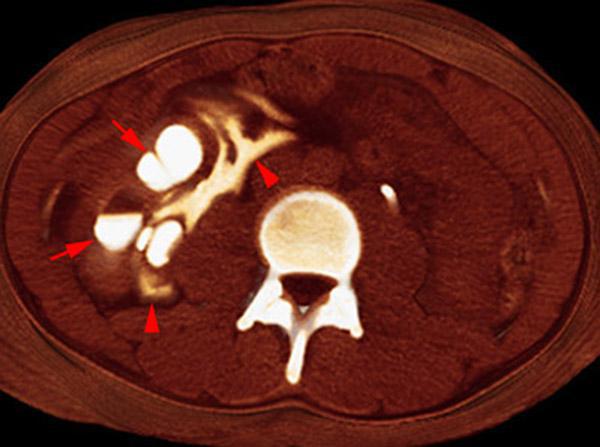

Rotura pielocalicial

VR seccional. Visión axial caudal. TC contrastado en fase excretora. Nefromegalia derecha. Hidronefrosis derecha (flechas) y extravasación urinaria (urinoma) en los espacios pararrenal anterior y perirrenal (puntas de flecha)